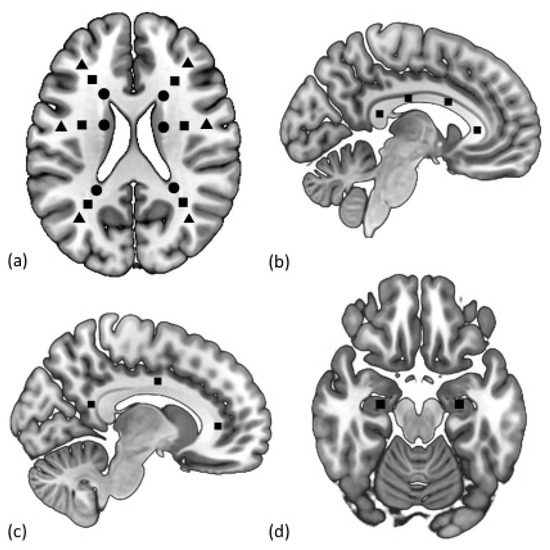

2. Materials and Methods

3. MRI Protocol and Imaging Analysis

3.2. Diffusion-Tensor Imaging